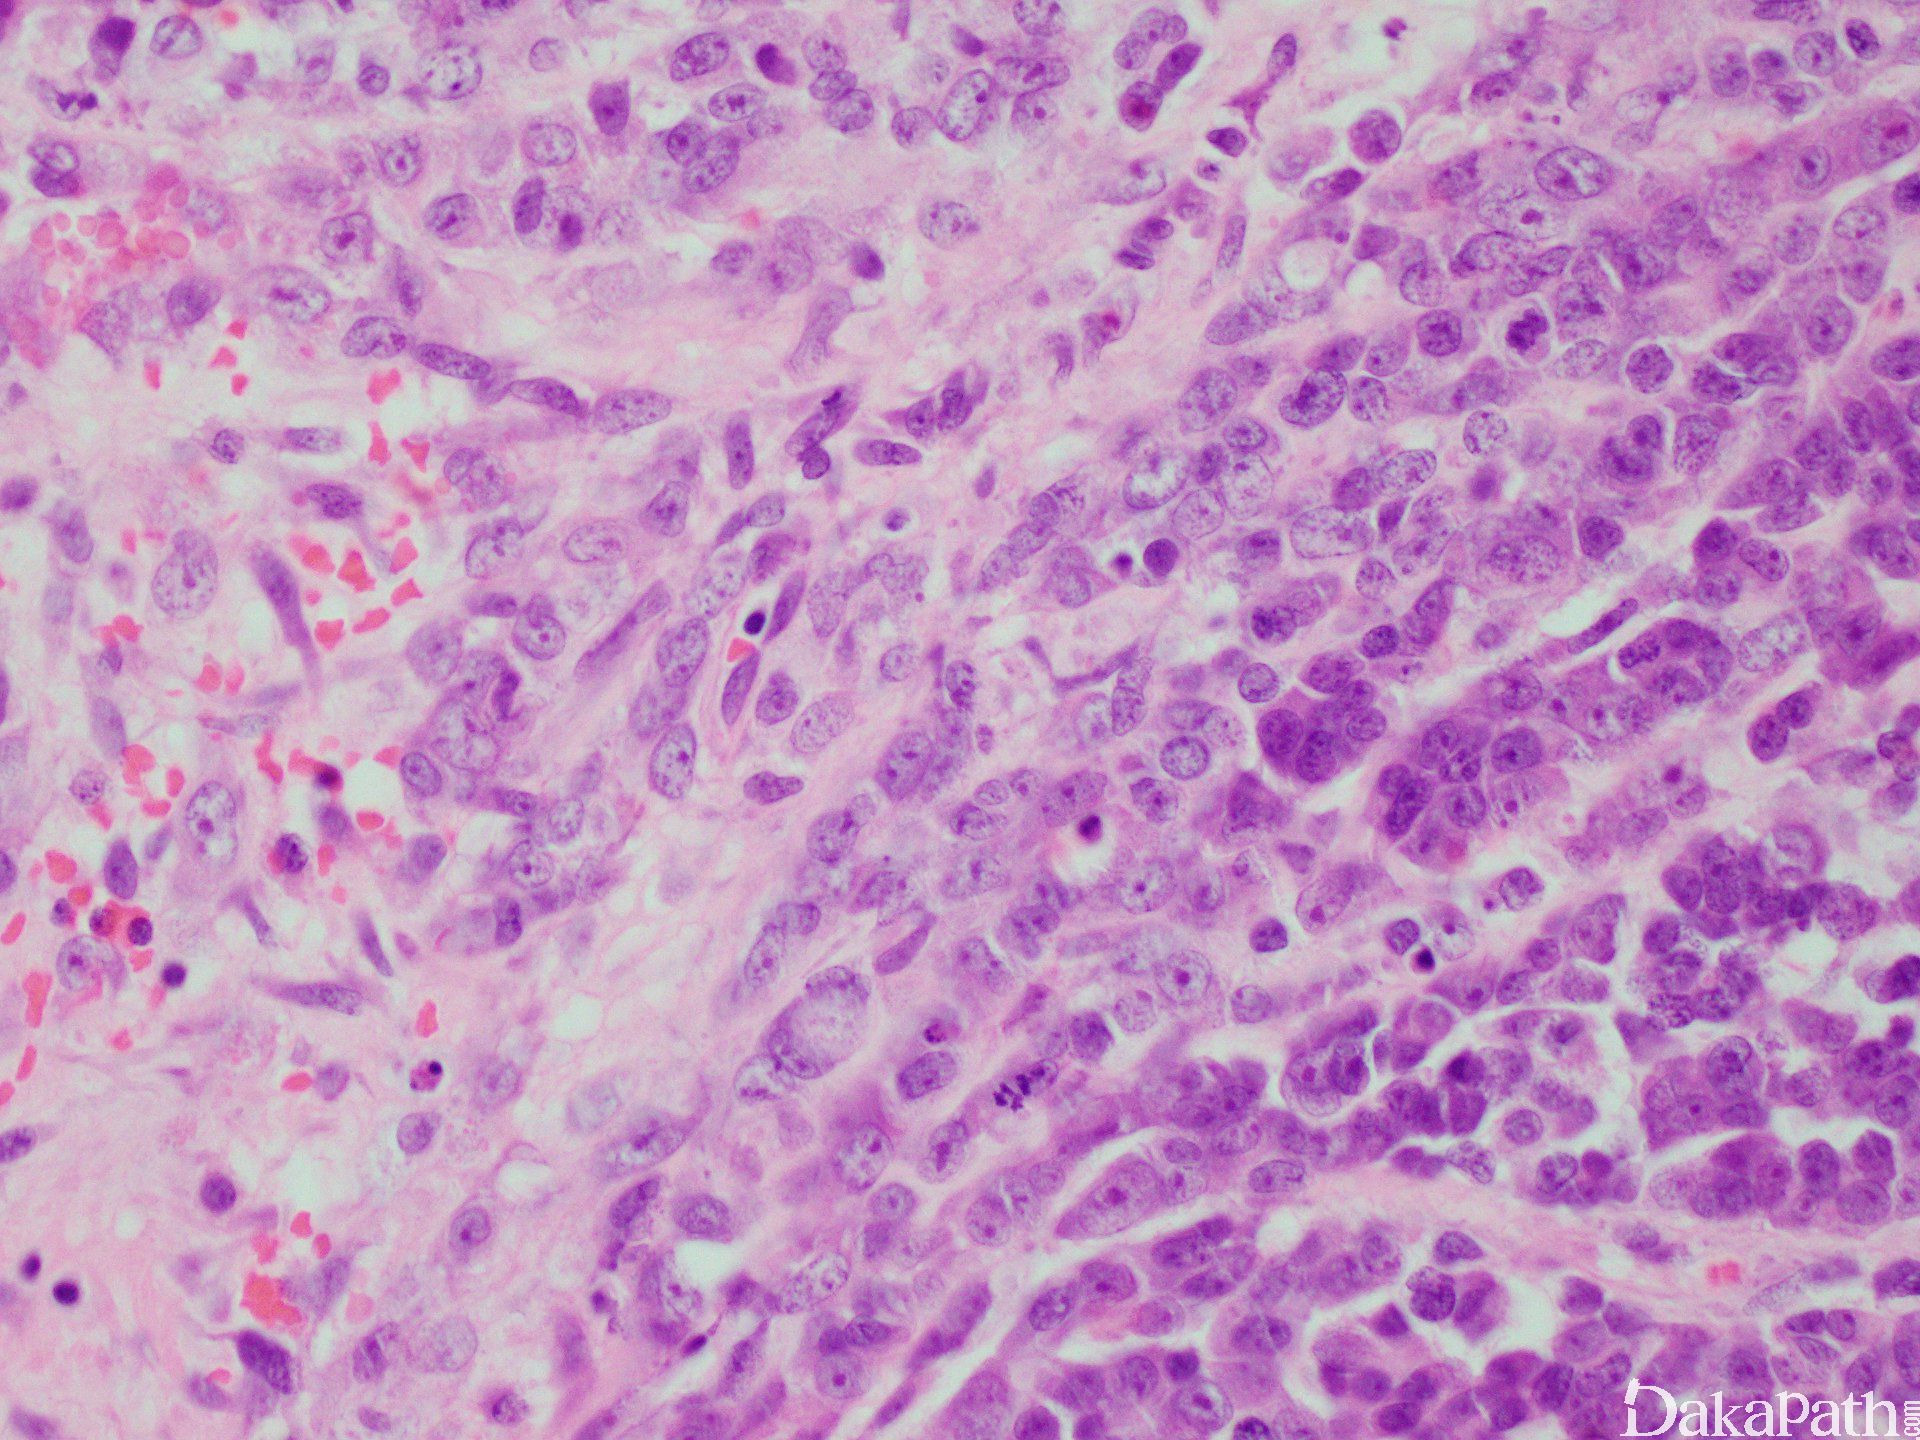

3. 细胞小或中等大,圆形至短梭形,胞质少,核深染,染色质似胡椒粉状,核分裂像多见, 坏死常见;

3. 组织学上,肺型小细胞癌的细胞具有匀细的染色质和不明显的核仁;而高血钙型小细胞癌的染色质呈块状、有明显的核仁,且40%的病例存在较大的细胞,胞质丰富、嗜伊红色;